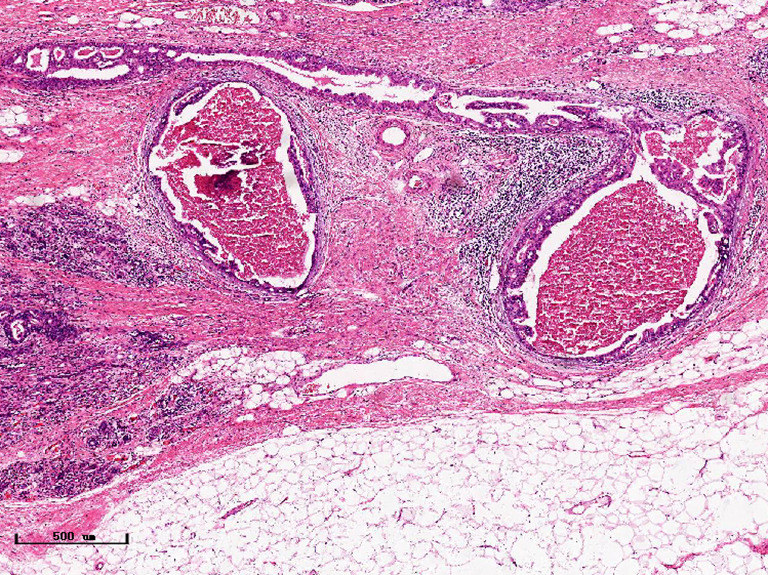

In this experiment, the measured value of the tumor bed of the control group and the measured value under the microscope have a large error. Compared with the experimental group, the error value is more unstable, and the difference is statistically significant. When the tumor bed is larger, the error in the control group is more obvious, but no obvious change in the experimental group, which proves that when the effect of chemotherapy is good and the tumor parenchyma is not obvious, there is a wide range of suspicious tumor beds. Sometimes, because the dense fibrous response at the edge of the tumor bed is not easy to distinguish from lower density cancerous lesions, the diameter measured at the outermost edge of the tumor parenchyma observed under the microscope is smaller than the macro measurement value (Figure 12), but CXS can solve this problem. CXS can play an accurate assessment role, when small focal tumors remain on the edge of the tumor bed, too small lesions are easily missed when the maximum diameter is plotted by the naked eye (Figure 13), and on X-ray imaging, they show strong signal points. Small lesions are therefore detected, which avoids the need for lesions omission. The shift of the tumor’s main body position after NACT is also a major factor affecting macro measurement, but CXS images can clearly find this phenomenon (Figure 14). One of the advantages of CXS is that it will appear as invasive cancer, DCIS, microcalcifications, and fibrous fat response under the microscope (Figures 15-17), and distinguish the images by different imaging signal densities.

Figure 12.

Presence of fibrous reactions at the edge of the tumor bed results in microscopic measurements less than macro/CXS measurements (hematoxylin and eosin). CXS, cabinet X-ray system.